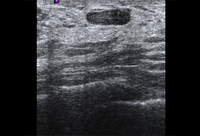

Avaliação de massa mamária

Imagem ultrassonográfica do espessamento da pele em paciente com câncer de mama inflamatório

Cortesia da Dra. Nancy Pile, Universidade de Louisville; usado com permissão